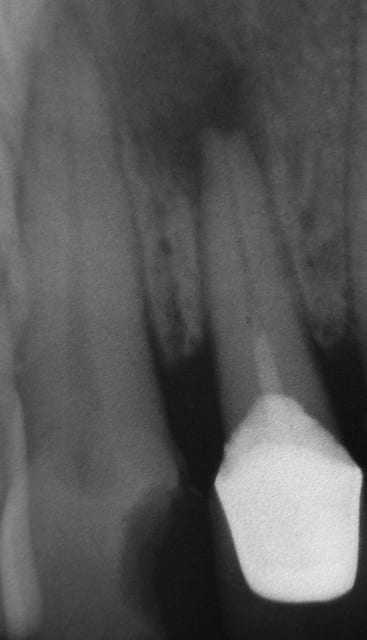

Patient qui tel, j’ai très mal sous le bridge que vous m’avais posé (23 24 25 en 2004, après dépose d’un bridge pour raison esthétique). Faut me voire aujourd’hui (lundi), elle arrive avec scanner des sinus fait en 2005, suite à des sinusites. Compte rendu du Radiologue, présence d'apex et d'Ag dans le sinus gauche, et que l’on peut rien faire et lui dit qu'au USA on fait des procès pour ça.

Je lui demande de me faire une pano, je cherche toujours les apex et les amalgames, par contre sans trop m’avancer je dirais qu’il y a la présence d’une dent, voir même d’une 28…..(que j’avais remarqué sur le scanner).